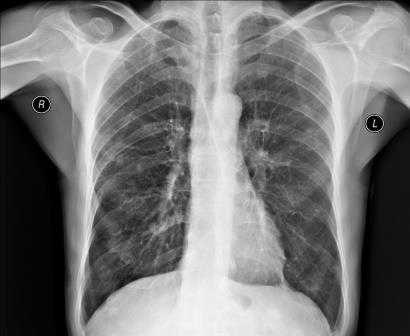

Рентгеном грудной клетки называют проекционное рентгенографическое обследование. Его цель - оценка патологии органов, находящихся в этой полости, и близкорасположенных анатомических структур. Данная разновидность рентгена является, пожалуй, одним из самых распространенных рентгенографических исследований. Рассмотрим подробнее этот тип аппаратной диагностики.

Органы и ткани человека по-разному реагируют на ионизирующее излучение: чем выше их плотность, тем светлее на снимке объект. Выполнение рентгенографии грудной клетки позволяет изучить мягкие ткани, кости этой части тела и анатомические структуры, находящиеся в исследуемой полости (легкие, плевру, средостение).

В зависимости от показаний пациенту может быть назначен обзорный или прицельный рентген грудного отдела. В первом случае получают изображения всех органов грудной клетки. На снимке обзорной рентгенографии хорошо видны дыхательные пути, лимфоузлы, сосуды, бронхи, трахея, легкие и сердце. Прицельная рентгенография направлена на исследование конкретного органа или его части и обеспечивает оптимальное изображение патологического очага для диагностики.

Результаты диагностик и расшифровка рентген-снимков грудной клетки

После получения изображения рентгенолог делает заключение и краткое описание снимка для врача, направившего пациента на обследование. В записи указывается, как расположено сердце, его размер (увеличенный или нормальный), какова его паренхима. Кроме того описывается состояние и остальных внутренних органов грудной клетки - легких, бронхов, сосудов и лимфатических узлов. Если снимок показал наличие посторонних предметов, затемнений или новообразований, это также отражается в заключении рентгенолога.

Во время расшифровки полученного рентгеновского снимка, прежде всего, оценивается качество изображения, а значит, и насколько правильно осуществлена процедура. Если рентгенография была сделана в неверной проекции и снимок имеет неточности, то заключение на его основании сделать достаточно сложно. При рентгене легких, например, оценивается размер легких, их форма, структура тканей и легочных полей, состояние воздушности и расположение внутренних органов.

Если у пациента пневмония, на снимке будут видны ярко выраженные отклонения от нормы - интенсивные дополнительные ткани как на прямой, так и на боковой рентгенограмме. Присутствие на снимке особой прикорневой формы, напоминающей по виду крылья бабочки, говорит о венозном застое в области малого круга. На отечность легочной ткани будут указывать неравномерные хлопьевидные затемнения на изображении.

Чаще всего врачу требуется рентгенограмма в прямой проекции, изображение в боковой проекции нужно значительно реже. При правильно проведённом обследовании четко заметны рёбра, сердце, органы дыхания, частично — кости плечевого пояса.

Рентгенография легких позволяет оценить их состояние размер, форму, структуру тканей, а также расположение прочих органов грудной клетки. Для получения наиболее полной информации о состоянии лёгких, врачу необходима рентгенограмма в 2 проекциях, где чётко просматривается лёгочная ткань, купола диафрагмы, тень сердца и органов средостения, кости позвоночника, плечевого пояса, грудины. Изображение различных органов и костей наложено друг на друга.

Для корректной расшифровки изображения необходимо четкое представление о том, как на рентгенограмме выглядят здоровые органы грудной клетки. К примеру, даже малозаметные затемнения, просветления, ассиметричный легочный рисунок может свидетельствовать о серьёзном заболевании. Регулярное проведение обследований позволяет выявить патологии на ранней стадии и незамедлительно приступить к лечению.

При анализе рентгенограммы следует чётко разделять заболевания, связанные с воспалением тканей, и туберкулёз лёгких. Туберкулома в большинстве случаев локализована на верхушках лёгочных путей, тень от неё округлая, чаще с просветлением в центре — очагом деструкции. Чётко заметны расширенные корни лёгких.

Воспаление лёгких (пневмония) чётко визуализируется на рентгенограмме. Выглядит как инфильтративная тень на фоне усиления рисунка лёгких, очаг пневмонии нередко окружен просветлениями — локальная компенсаторная эмфизема.